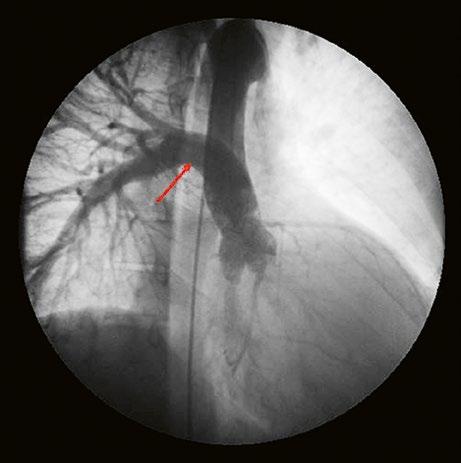

Supravalvární pulmonální stenóza a stenózy větví plicnice bývají součástí komplexních VSV (např. Fallotovy tetralogie) nebo syndromů (Williamsův syndrom, syndrom Noonanové, syndrom vrozené rubeoly, Alagillův syndrom aj.) (Obr. 45.39). Získané stenózy větví plicnice, ale i úplný uzávěr větve plicnice můžeme vidět po spojkových operacích podle BlalockaTaussigové (Obr. 45.40, Obr. 45.41). Pro zobrazení supravalvárních a periferních stenóz plicnice je optimální CT angiografie (Obr. 45.40, Obr. 45.41, Obr. 45.42, Obr. 45.43).

Obr. 45.41 Uzávěr levé větve plicnice jako následek provedené spojky podle BlalockaTaussigové v dětství, CT angiografie